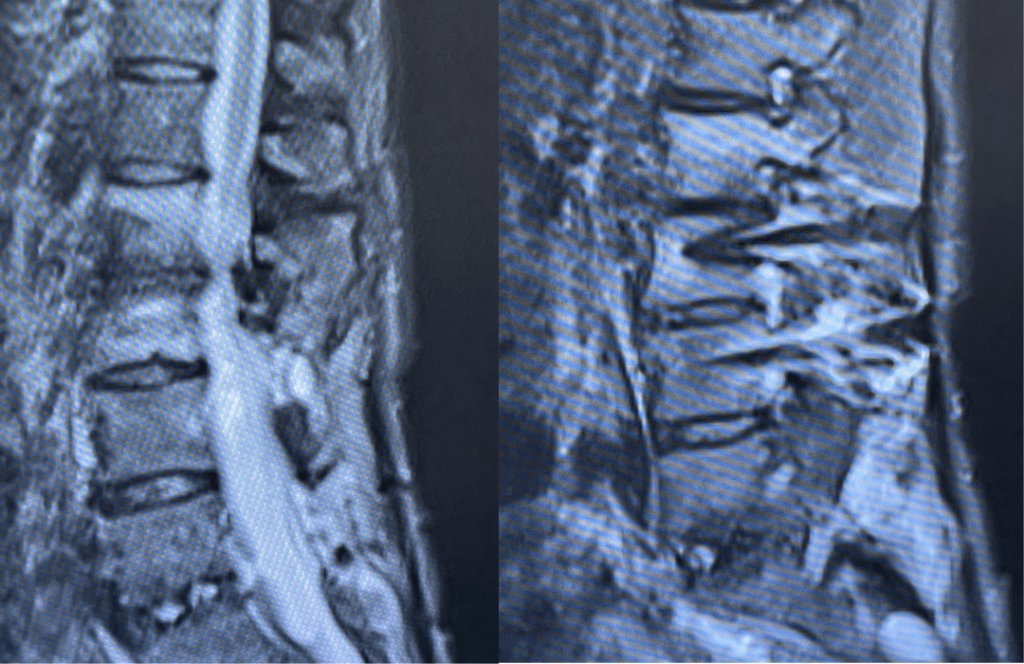

This 62-year-old female presents with chronic intractable low back pain with radiation down the front of her thighs. The patient had had two prior fusion surgeries: She initially had an L4-S1 fusion twelve years prior and a subsequent revision extension of her fusion at L3-4 that she had three years prior. She had a long-term history of smoking. She had mild hip flexor weakness, right greater than right. Imaging studies revealed next segment degeneration and stenosis at L2-3. (Figs. 1a and 1b and 2).

Figure 2. Axial T2 MRI of the lumbar spine demonstrating L2-3 stenosis due to significant facet arthropathy.